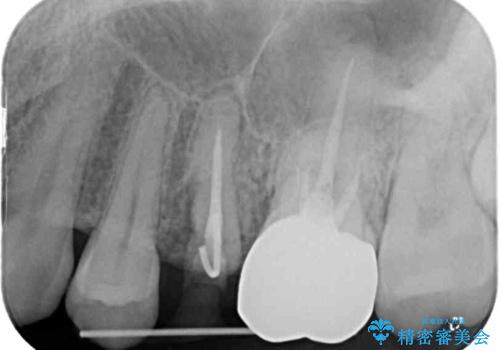

- 他院で大きな虫歯の歯を引っ張り出す治療中、あまりにも異臭がするとのことで来院された患者様です。

診査したところ、虫歯が広範囲で、粗造になった歯の表面に汚れがこびりついていました。また、歯根の半分以上の深さにまで亀裂が生じており、保存は不可能と診断しました。

抜歯後に治癒を待って、フルジルコニアブリッジにて補綴することとしました。